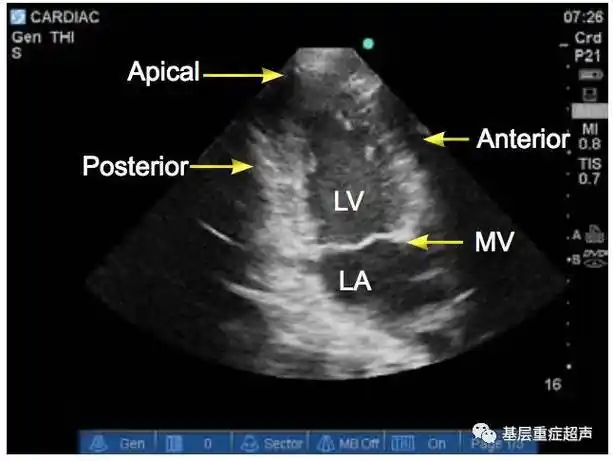

超声心动图切面介绍胸骨旁长轴胸骨旁短轴心尖切面剑突下切面